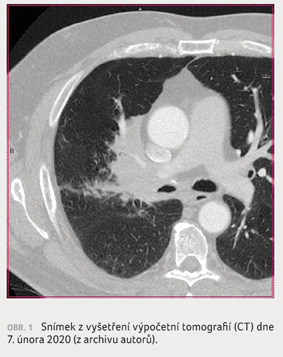

U pacienta ve věku 57 let byl v únoru 2020

(obr. 1, 2A–D) diagnostikován lokálně

pokročilý plicní adenokarcinom, rozsahu a stadia T4N2M0,

stupně IIIA, s postižením distální části pravého

hlavního bronchu a kmene plicnice. Onemocnění bylo

neřešitelné radikální resekcí pro víceetážové postižení

mediastinálních uzlin. Exprese PD L1 byla pozitivní v 60 %

nádorových buněk, mutace ALK a ROS byly negativní. Mutace

receptoru epidermálního růstového faktoru (EGFR) nebylo možno

stanovit pro nedostatek materiálu. Pacient podstoupil radikální

CChRT; chemoterapii ve složení vinorelbin, cisplatina (schéma

dle Zatloukala [10]) na Klinice pneumologie a ftizeologie

v Plzni, souběžně s radioterapií tumoru pravé plíce,

pravého hilu plicního a mediastinální lymfadenopatie

(skupina 4 a 7) v dávce 66 Gy – léčba probíhala

do července 2020 na Onkologické a radioterapeutické

klinice FN Plzeň. Bezprostředně po ukončení ozáření bylo

indikováno kontrolní CT hrudníku, které prokázalo parciální

remisi onemocnění (obr. 3). Následovalo adjuvantní